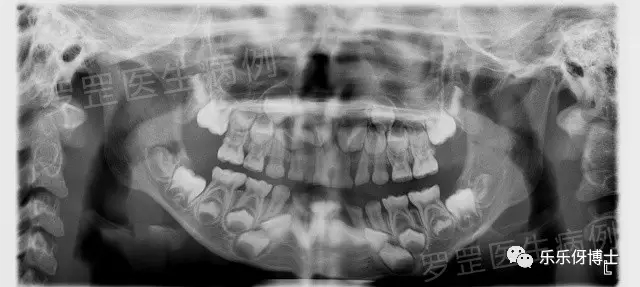

2.拍片

(口腔全景片)

如果家长选择了某种形式,医森初诊当天会安排助手给小朋友拍摄口腔全景片&头颅侧位片,可以更加准确了解小朋友牙齿生长发育情况及骨骼发展情况,以便更好制定正畸方案。